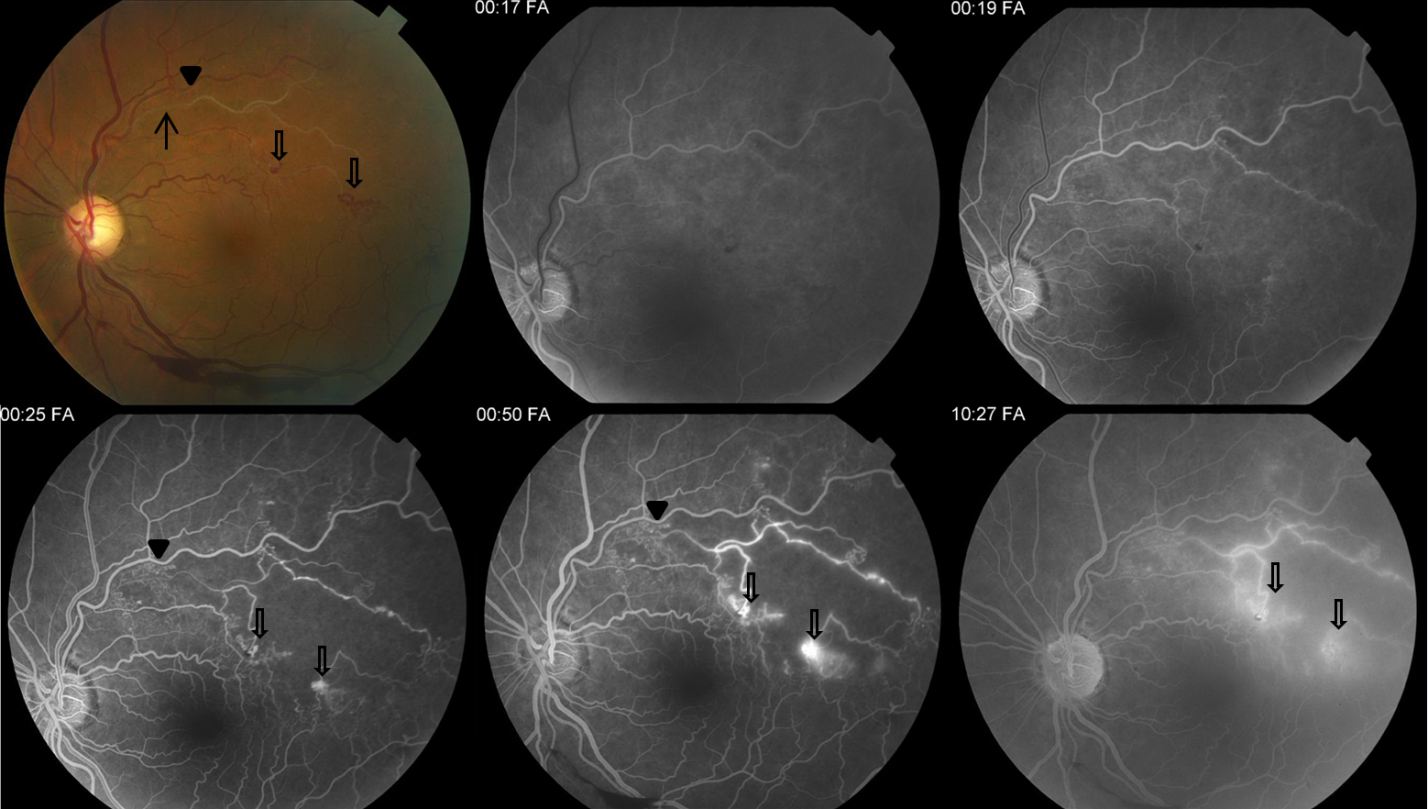

Color fundus photograph and series of fluorescein angiograms showing chronic branch retinal vein occlusion with sclerotic superotemporal arcade vessel (arrow). There small collateral vessels (black arrowhead) that can be confused with neovascularization but do not leak on FA. There is also significant surrounding capillary nonperfusion and areas of neovascularization with leakage (open arrows).